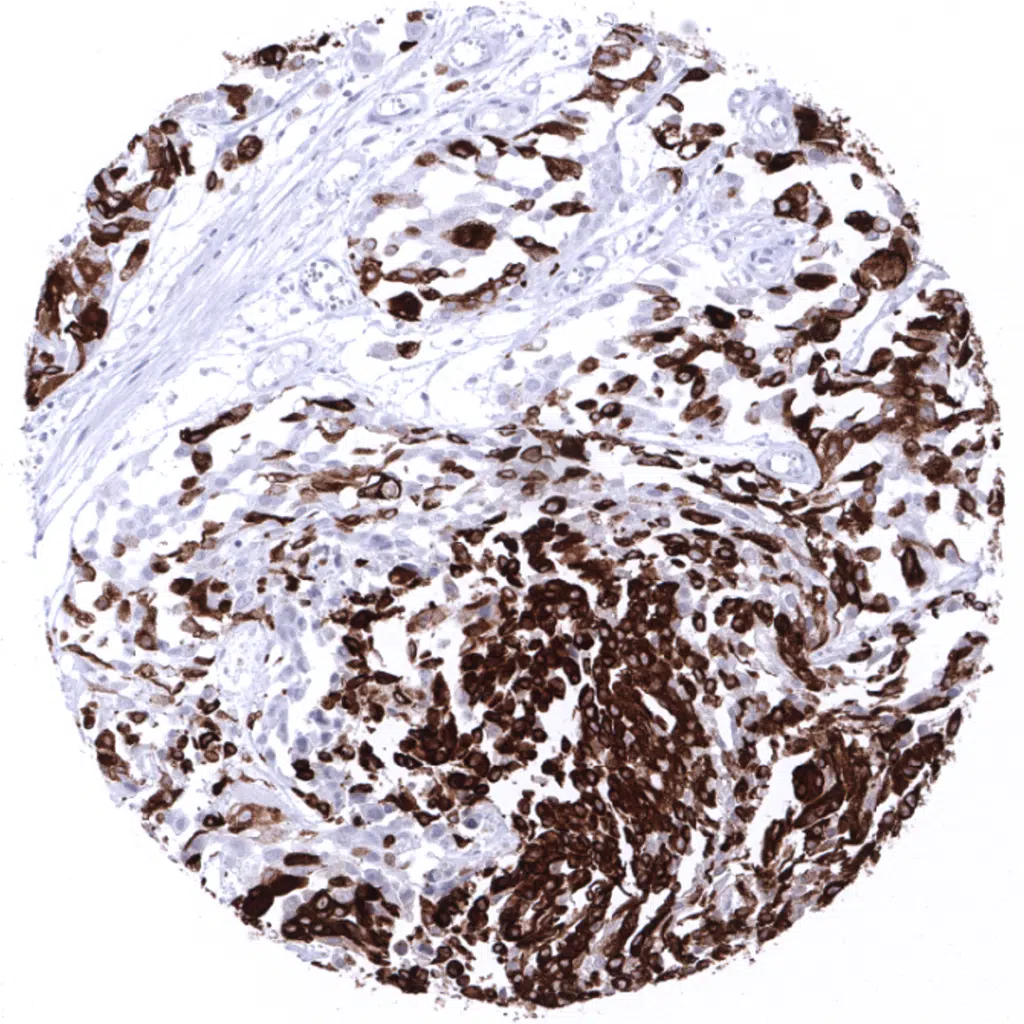

Colon- Strong diffuse MUC5AC immunostaining in a colorectal adenocarcinoma.